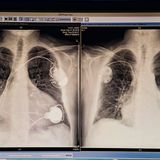

• Organspende - Gerd und sein neues Herz

Fotostrecke: Gerd kämpft sich zurück ins Leben. Die Zeit nach der OP in Bildern